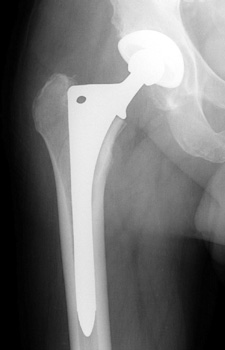

Intraoperative fracture of the proximal femur.